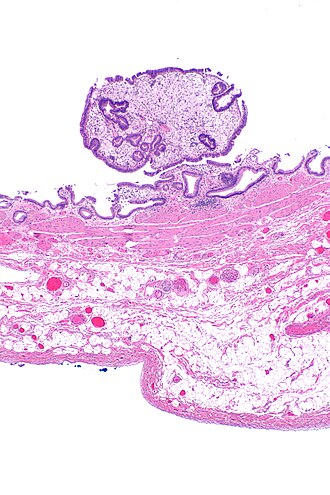

Cholesterol polyp of the gallbladder

Cholesterol polyp of the gallbladder. H&E stain. | |

| LM | foamy macrophages in lamina propria of polypoid lesion |

| Gross | polypoid lesion of gallbladder mucosa |

| Site | gallbladder |

Cholesterol polyp of the gallbladder is a common benign finding of the gallbladder.

- Exophytic lesion of the gallbladder mucosa.

- Foamy macrophages in the lamina propria.